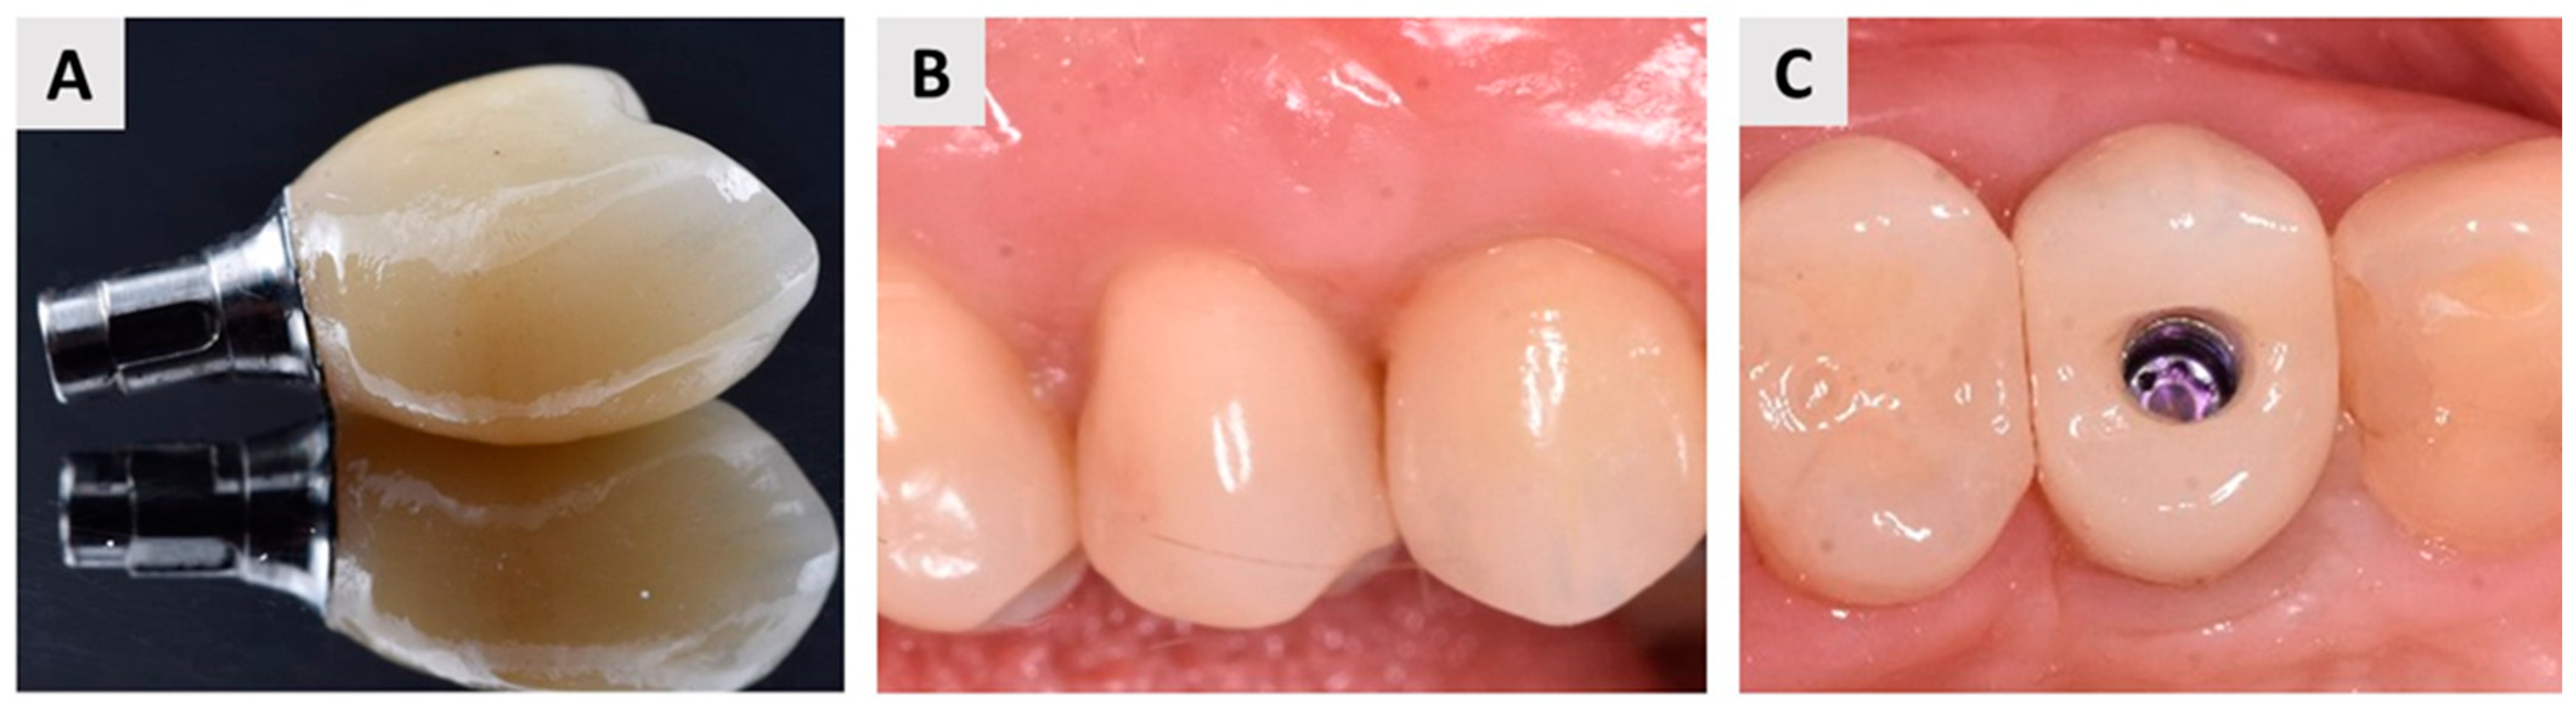

2.5. Dental Implant Placement and Bone Biopsy Harvesting

3. Results

3.1. Clinical Outcomes